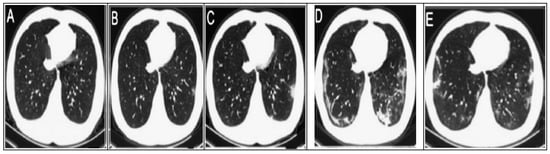

- Li, X.; Zeng, W.; Li, X.; Chen, H.; Shi, L.; Li, X.; Xiang, H.; Cao, Y.; Chen, H.; Liu, C.; et al. CT imaging changes of corona virus disease 2019(COVID-19): A multi-center study in Southwest China. J. Transl. Med. 2020, 18, 1–8. [Google Scholar] [CrossRef] [PubMed] [Green Version]